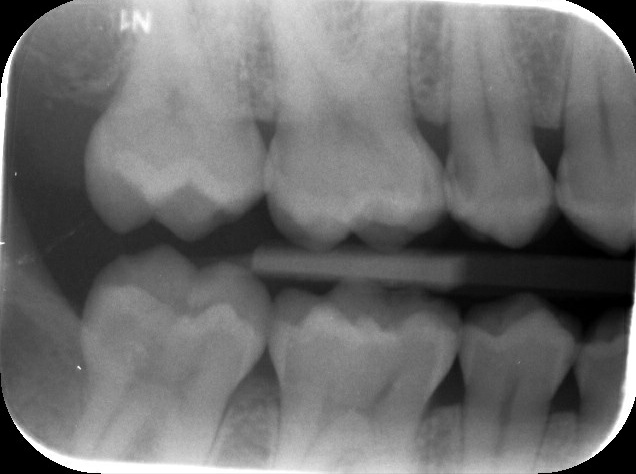

Ik ben vandaag bij een nieuwe tandarts geweest ivm verhuizing. Deze heeft geconstateerd dat mijn tandglazuur vrijwel verdwenen is, want dat is onder meer te zien aan de witte vlekjes aan de onderkant van mijn kiezen en daarnaast heb ik enkele gaatjes in mijn kiezen zowel rechts als links en boven en onder. Ik moet hem maar op zijn woord geloven, maar als ik deze foto's zie...dan zie ik geen gaatjes. Althans, ik ben geen tandarts hoor maar aan gaatjes dan zie je toch iets van een zwarte vlek of andere oneffenheden? De behandeling die hij voorstelde is: V92-A10 / V92-A10 / V92-A10 / V91-A10 / V91 / V92. Kostenplaatje zo'n 375 EU. Dit is een hoop geld en wil zeker weten of hij het bij het rechte eind heeft alvorens ik akkoord geef. Klopt het de begroting die hij voorstelde? Alvast bedankt!

Ik zie 6 gaatjes in 5 kiezen.

35 - 15 - 14 - 45 - 44 - 16

36 100% zeker ook. 24 heb ik